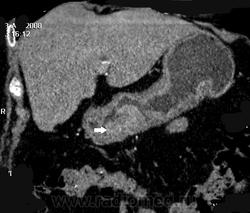

Однако наиболее распространенным является применение КТ для диагностики и дифференциальной диагностики очаговых поражений печени и поджелудочной железы. Стандартным является выполнение КТ с болюсным введением 100-140 мл контрастного средства. Многофазное исследование в различные фазы контрастирования (из которых важнейшими являются артериальная и портально-венозная) позволяет выявлять и характеризовать очаговые поражения печени и поджелудочной железы, планировать лечение и оценивать его результаты. С помощью МСКТ можно с высокой точностью визуализировать артерии и вены органов брюшной полости, а также желчные протоки.

323: 67-летний мужчина представляет с потерей веса, усталостью и желтухой. [1 из 2]

324: 67-летний мужчина представляет с потерей веса, усталостью и желтухой. [2 из 2]